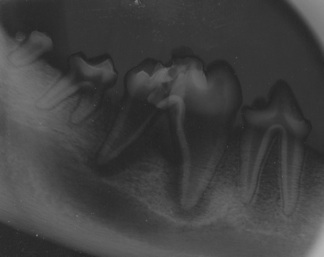

effetti del gioco con le pietre